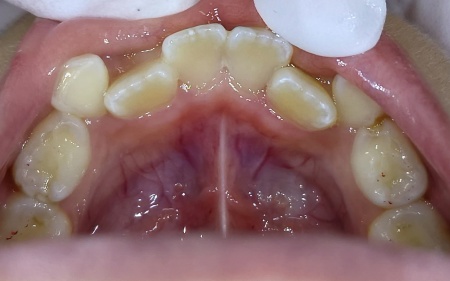

治療前

「下前歯の裏が黄色い」とご相談いただきました。

カウンセリング・診断結果

拝見したところ、下前歯の裏側に歯石が多く付着していました。